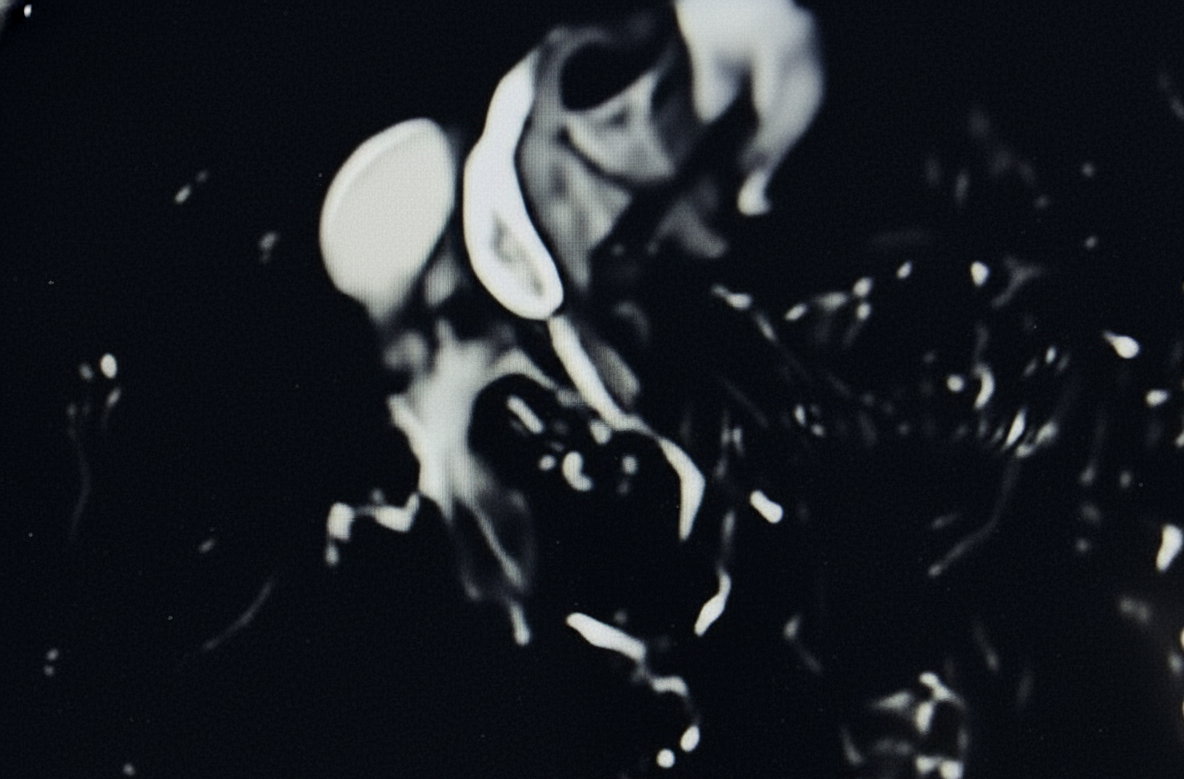

Magnetic resonance cholangiography (MRCP) revealed mild intrahepatic bile duct dilatation in both hepatic lobes, a tight anastomotic stricture of the common bile duct, and dilation of the common bile duct above the bilio-biliary anastomosis up to 11 mm (Fig. 1).

Selective cannulation of the common bile duct (CBD) was achieved using a 0.025-inch guidewire-assisted sphincterotome. Injection of radiopaque contrast revealed a tight mid-choledochal stricture, associated with mild intrahepatic bile duct dilatation. The CBD was dilated above the biliary anastomosis up to 11 mm, with the distal CBD measuring 6 mm. A wide endoscopic sphincterotomy was performed, and attempts were made to advance a 0.025-inch guidewire—both angled and straight—into the intrahepatic biliary tree; however, the anastomotic biliary stricture could not be traversed. Subsequently, the SpyGlass cholangioscope was introduced, enabling direct visualization of the biliary anastomotic stricture and successful passage of the 0.025-inch guidewire across the stenotic segment into the intrahepatic bile ducts. Balloon dilation of the biliary stricture was then performed using a 6/40-mm balloon under combined cholangioscopic and fluoroscopic guidance. Following endoscopic bilioplasty, the cholangioscope advanced through the stricture easily, and tissue samples were collected from the choledochal anastomosis (Fig. 2 and Video 1). A fully covered 8/80mm biliary self-expanding metal stent (SEMS) was subsequently placed, followed by insertion of a 10 Fr/5cm double-pigtail plastic biliary stent through the SEMS to prevent migration of the fully covered stent (Fig. 3, Fig. 4).